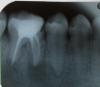

Artem32 Опубликовано 8 сентября, 2012 Поделиться Опубликовано 8 сентября, 2012 Пару дней назад внезапно заболел зуб, который давно в детстве лечили и пломбировали и все эти годы все было хорошо. Но теперь малейшее нажатие на него вызывает еще более сильную боль.Сделали снимок, стоматолог не увидел ничего плохого, а вот хирург стоматолог увидел на снимке 2 кисты под корнями зуба, и сказал однозначно удалять. Но я никак не могу смириться, все же жевательный зуб, как без него... и жертвовать двумя соседними ради моста (или как это называется), тоже ужасно.Скажите, нет ли другого пути ? Ссылка на комментарий

Doc Опубликовано 8 сентября, 2012 Поделиться Опубликовано 8 сентября, 2012 По одному снимку сложно что-то советовать, но кажется там уже ловить нечего. Помимо кист там еще и отломанный корень видится. Будете тянуть - потеряете еще много полезной кости, которая потом очень пригодится для имплантации. Поставите хороший имплантат и надолго про эту проблему забудете. Ссылка на комментарий